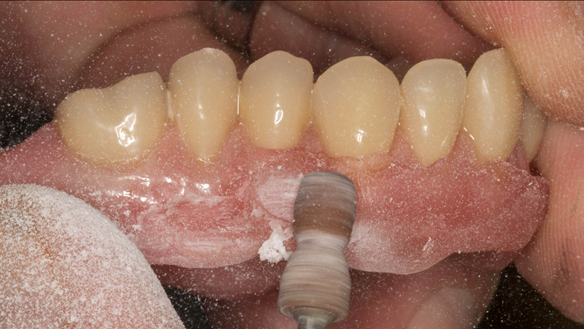

This newsletter describes in step by step detail Anne's transition from an immediate complete upper denture to a definitive complete upper denture.

This 73 year old woman was referred to me by her general dental practiioner for treatment.

- The remaining natural upper natural teeth and lower back molars were heavily restored having generalised periodontitis stage 4 Grade C. Some of the teeth exhibited caries. The prognosis for these teeth ranged from dubious to hopeless.

The clinical situation and treatment process is shown in detail below with photographs. In addition, threre is a link to the a 45 minute webinar I gave explaing this case. I provided the clinical work and Rowan Garstang provided the technical work.